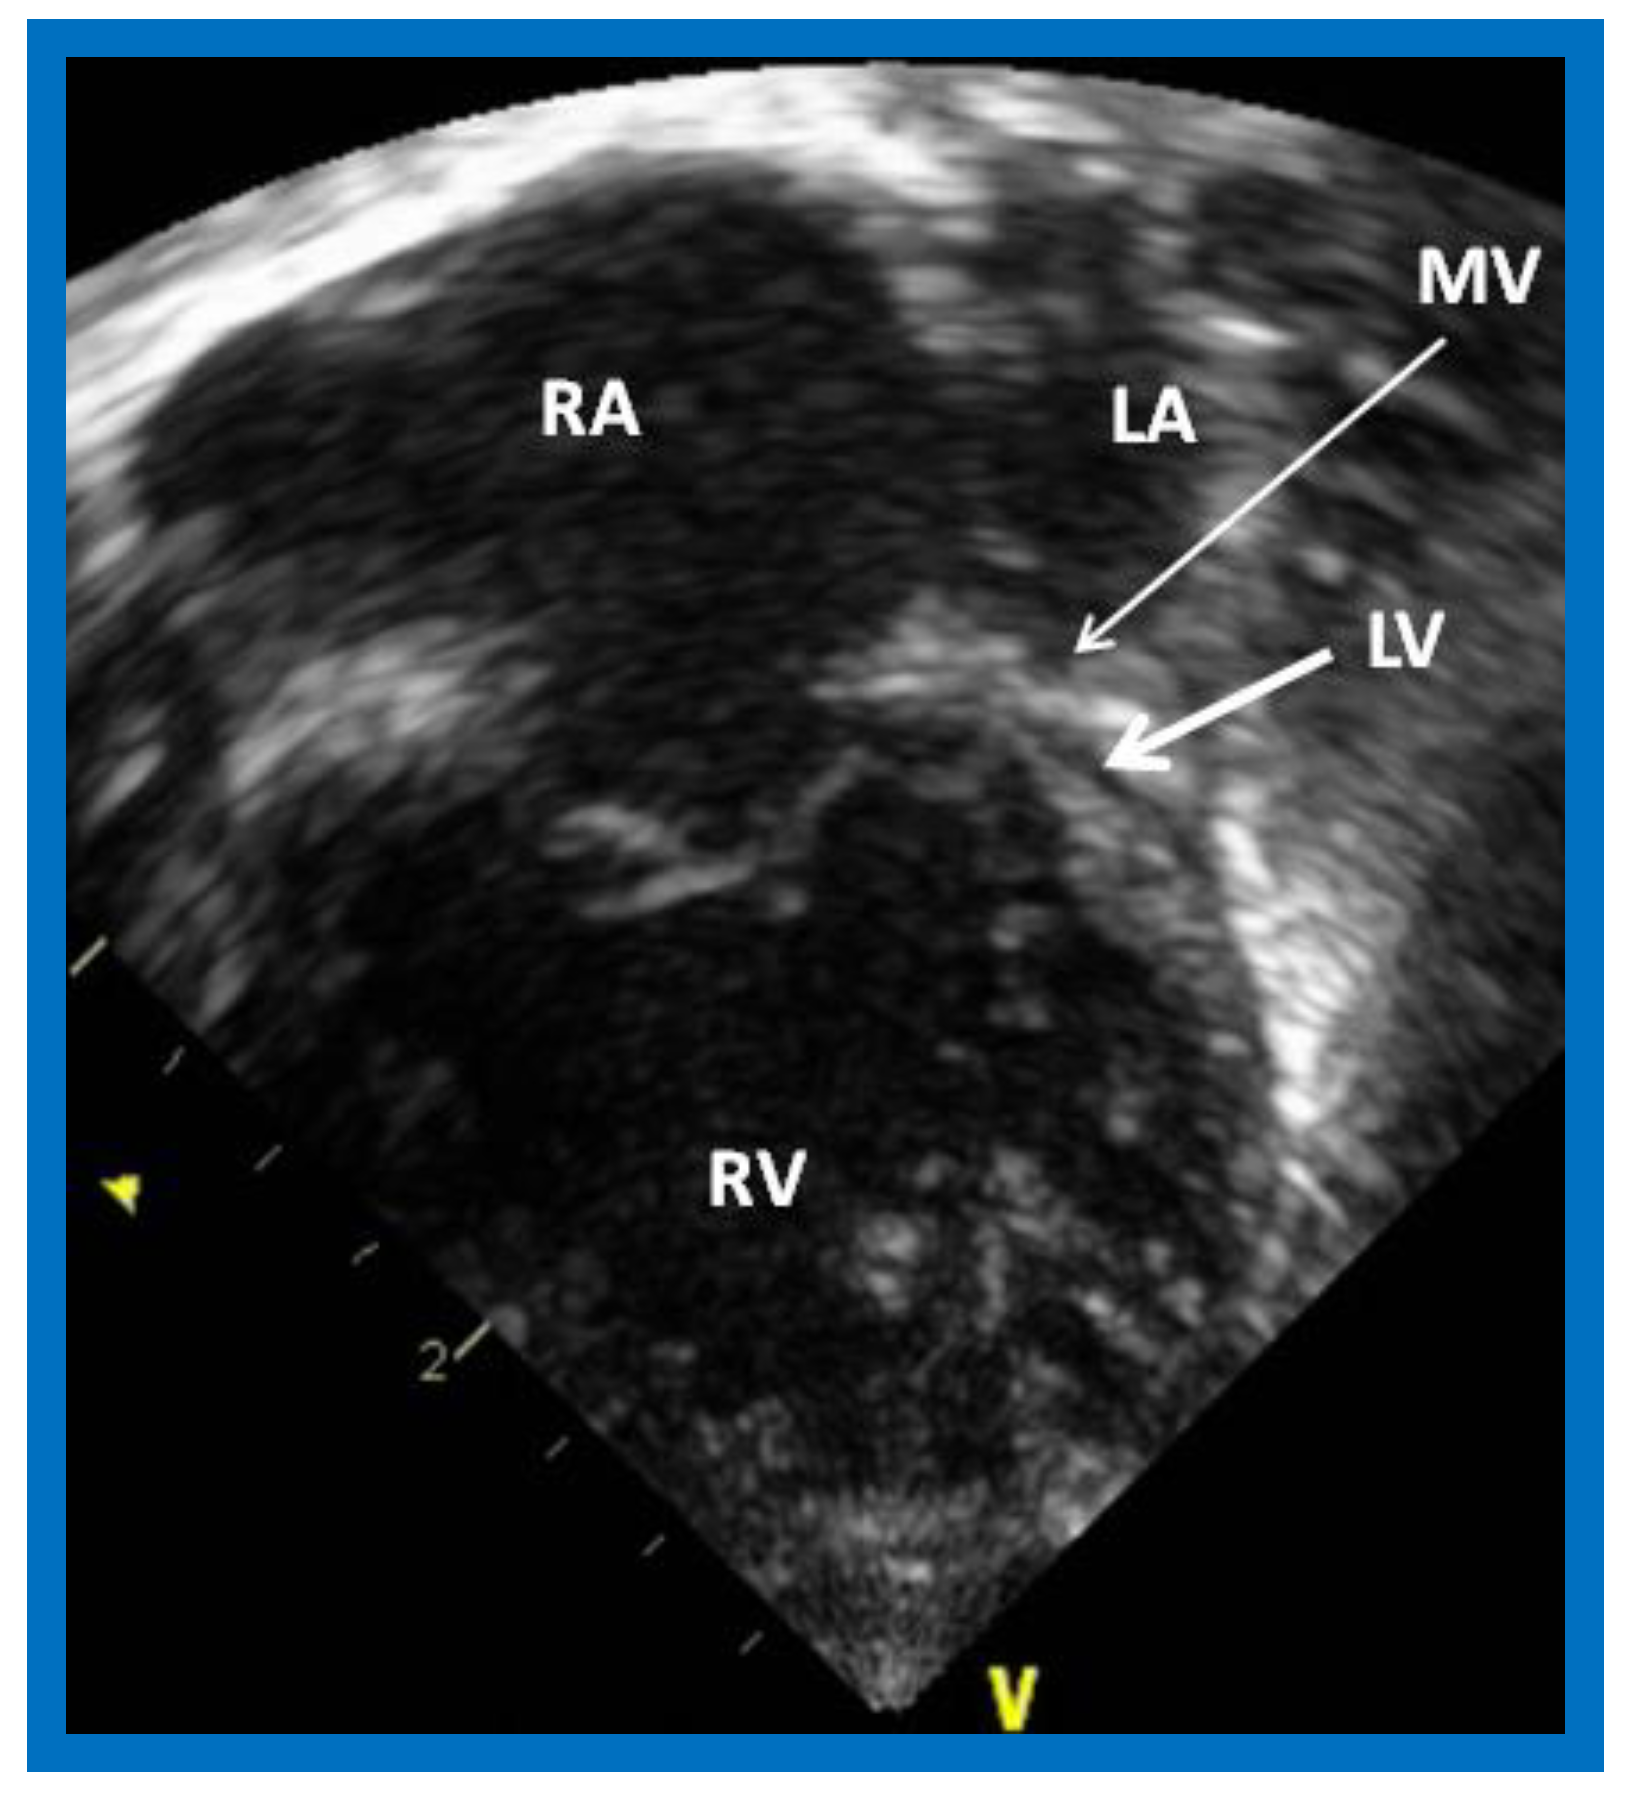

Figure 1.

Echocardiogram in an apical 4-chamber view of a baby with hypoplastic left heart syndrome, showing a strikingly small, slit-like (thick arrow) left ventricle (LV), obviously enlarged and hypertrophied right ventricle (RV), and a dilated right atrium (RA). The atretic mitral valve (MV) (thin arrow) and hypoplastic left atrium (LA) are also seen.